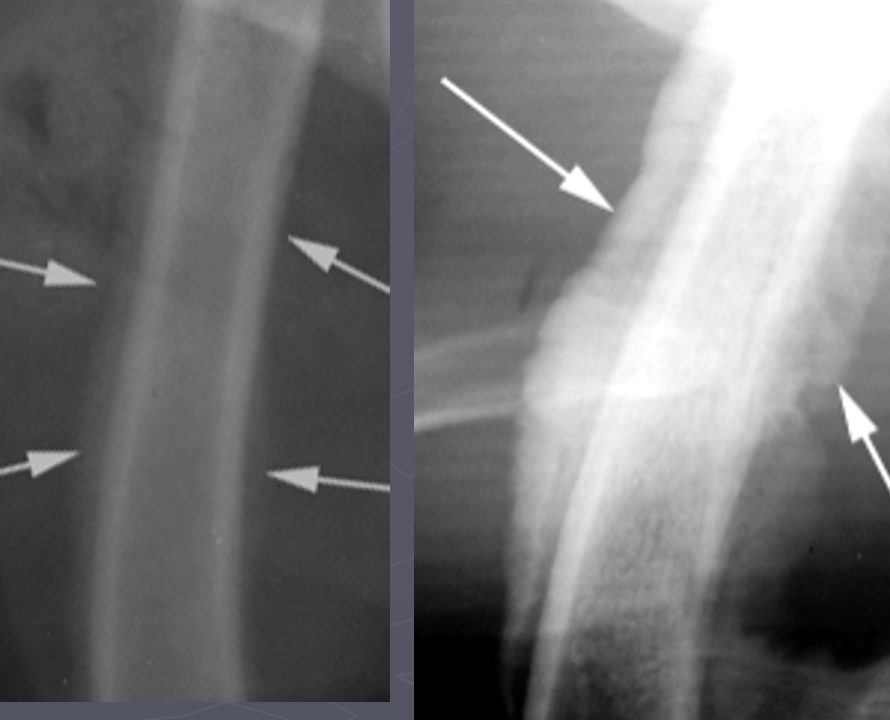

9

What is shown in these radiographs?

A

lamellated periosteal reaction

What are the characteristics of lamellated periosteal reaction?

-layered or “onion skin” appearance

-indicates cyclic or intermittent process

-more aggressive than solid/smooth new bone

-occurs with stress fracture, osteomyelitis, or hypertrophic osteopathy

-transient feature of normal growth